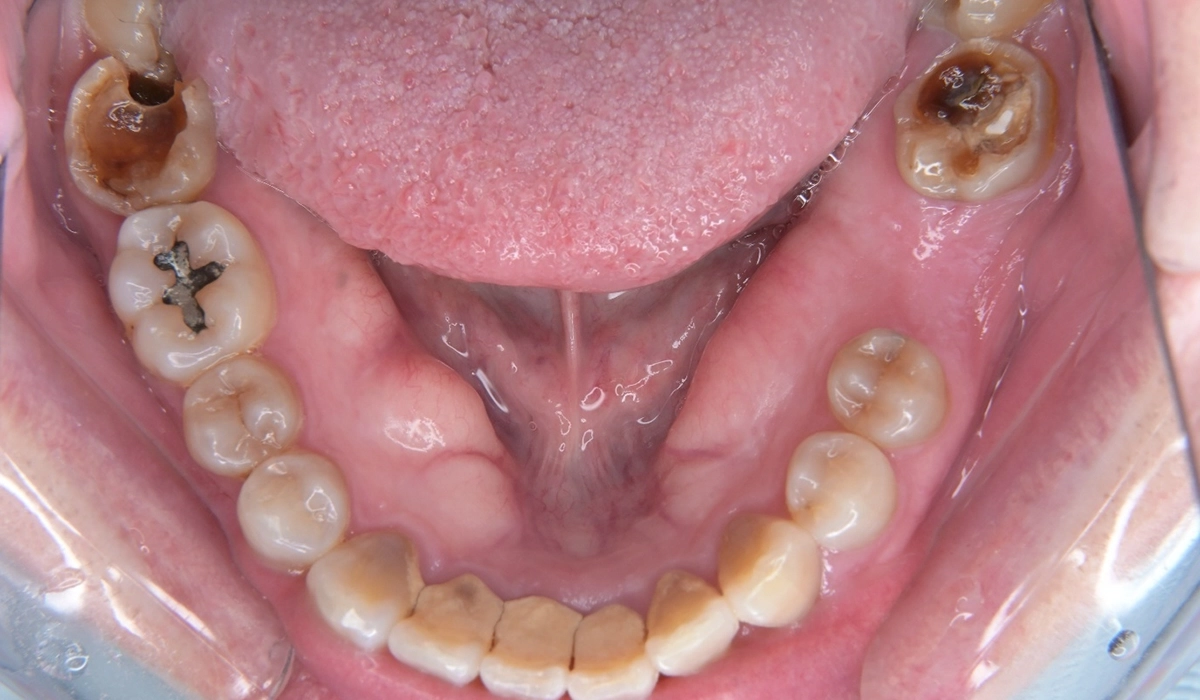

こちらが術前の口腔内写真になります。

問題点としては前歯部、臼歯部で進行したカリエスおよび前歯部歯肉増殖症、広範型慢性歯周炎StageⅡ GradeAが挙げられます。本症例では前歯部の審美性の回復について患者様との話し合いのうえセラミック修復による治療を選択しました。

歯周環境の改善のために親知らずの抜歯を適宜行っています。